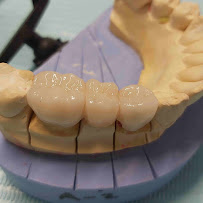

• Restorative Dentistry: Composite and amalgam fillings, inlays, onlays, crowns, and bridges

• Prosthodontics: Full and partial dentures and implant-supported prosthetics